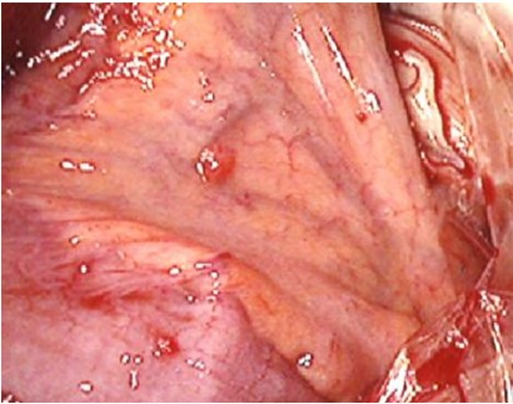

From 2006 to 2023, 107 patients with MPM were referred to our hospitals, and 9 (8.4%), 84 (78.5%), 9 (8.4%) and 5 (4.7%) were pathologically classified into WDPM, epithelioid, biphasic, and sarcomatoid type, respectively, according to the classification of WHO from biopsied materials and resected specimens. Among 9 WDPM patients, 5 were male and 4 were female, and the age range from 35 to 65 with mean age of 45.1 years old (Table 1). Case one showed scattered nodules (5 small nodules of smaller than 5 mm in diameter on the small bowel mesentery and one nodule of 6 mm in diameter on the caecum) (Figure 1). Biopsied material showed typical papillary architecture containing fibrovasular cores with a single lining of cuboidal mesothelial cells without atypia or mitoses on the peritoneal surface. She was treated by Laparoscopic Hyperthermic Peritoneal Chemotherapy (LHIPEC) with 20mg of mitomycin C (MMC) and 100mg of cisplatinum (CDDP) (Tables 1,2). She is alive without recurrence 7 years after LHIPEC.

Figure 1: Scattered type of WDPM (case 1), 2-3 mm of several nodules were found on the small bowel mesentery.

Microscopic examination showed that a papillary pattern accompanied by a glandular pattern, and the papillary areas were lined by a single cuboidal mesothelial cells (Figure 3), with one case (Figure 4, Case 8), having a mild nuclear atypia. In general, the mesothelial cells lacked mitotic activity. In addition, less than 1% of cells were positive for MIB-1 antibody (Figure 5). Immunohistologic studies showed a positive calretinine, CK7 (Figure 6) and D2-40 (Figure 7) and a negative CEA. In case 8, submesothelial invasive tumor of higher cytologic grade was detected in one of 23 sections from resected specimen.

Figure 3: Hematoxilin-eosin staining of case 4 (left) and case 1 (right).